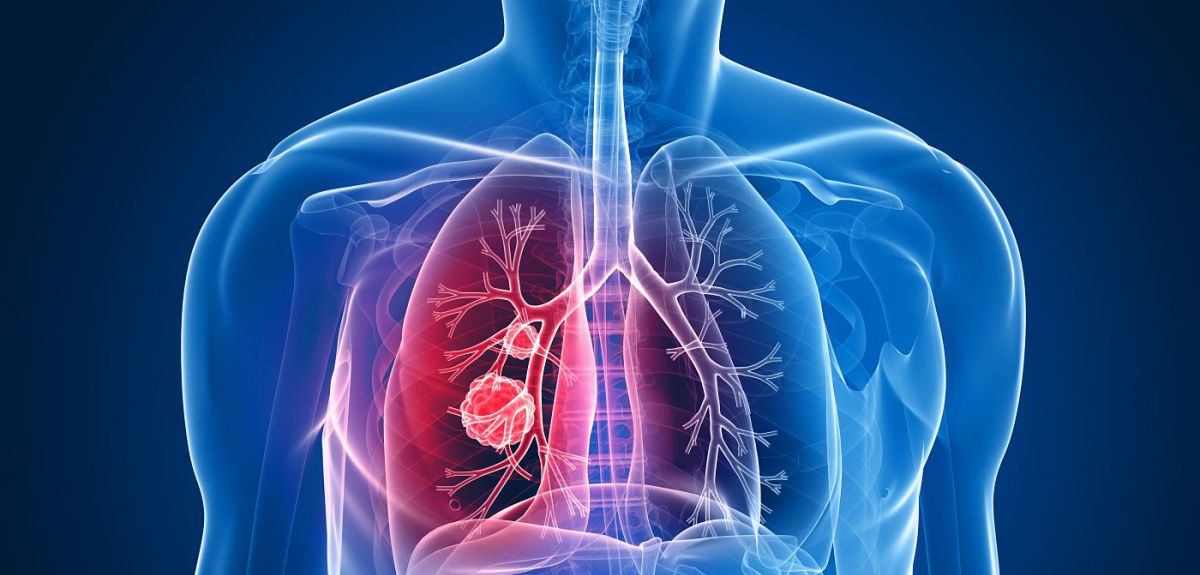

Κοροναϊός : Υποδοχείς των πνευμόνων η ενδεχόμενη πύλη εισόδου του στον οργανισμό

Υπάρχει μια υποψία ότι ο κοροναϊός μπορεί να εισέρχεται στον οργανισμό μέσω κάποιων υποδοχέων στους πνεύμονες, και μάλιστα ίσως κάτι τέτοιο να είναι αυξανόμενο σε υπερτασικούς